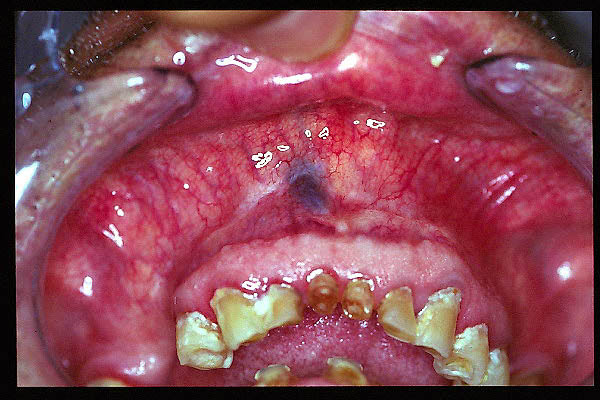

CM Estomatitis protésica